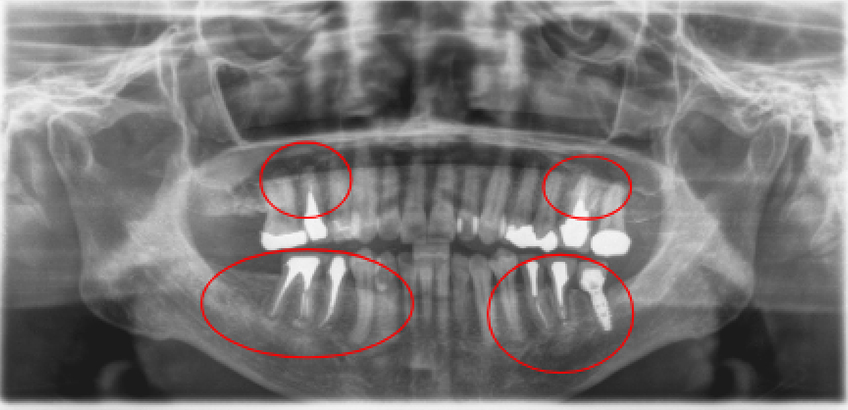

2008年03月 初診時

2008年06月 歯周基本治療終了後

2016年6月 約4年経過

2023年12月 上顎残存歯

最終補綴処置終了後 約2年経過

| 治療内容 | 重度歯周病・インプラント・矯正治療 |

|---|---|

| 患者様の年齢 | 52歳 |

| 患者様の性別 | 男性 |

| 治療期間 | 初診時より4年 |

| 治療回数 | 矯正治療・歯周治療・インプラント治療合わせて130回程度 |

| 治療費用 | インプラント:約450万円/歯周病:15万円 矯正:15万円/補綴治療:110万円 |

| 治療で得られるメリット |

|

| 治療する際に起こる リスク・副作用 |